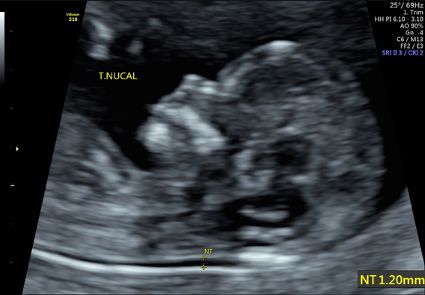

A detecção de mielomeningocele no pré-natal tem se tornado cada vez mais precoce. O diagnóstico já pode ser suspeitado precocemente entre 11 e 14 semanas de gestação no Ultrassom Morfológico de 1º Trimestre (também conhecido com Ultrassom da Translucência Nucal) por meio de marcadores específicos que são avaliados nessa idade gestacional e confirmado a partir do 2º Trimestre de gestação!

![]()

Figura 2: Feto de 12 semanas de idade gestacional em Ultrassom Morfológico de 1º Trimestre em que é possível rastrear a mielomeningocele por meio de marcadores específicos dessa fase.

Figura 3: Ultrassom evidenciando a lesão na coluna do feto de 22 semanas de gestação. Mielomeningocele lombo-sacral.